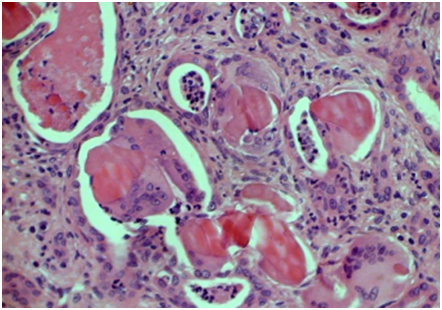

MM patients had different pathology patterns: mainly AL amyloidosis (Figure 5) and CN (Figure 6), but also LCDD/HCDD (Figure 7), SI and DNS. Interestingly, we had a case of MM with three types of lesions-CN, LCDD and AL, showed by two consecutive pathology studies. WM patients were found to have AL, Cryo GN (Figure 8), GN with monoclonal IgM deposits (Figure 9), MN and FSGS.

Figure 6 Cast-nephropathy PAS х 250.

Figure 8 Cryoglobulinemic glomerulonephritis, PAS x 250.